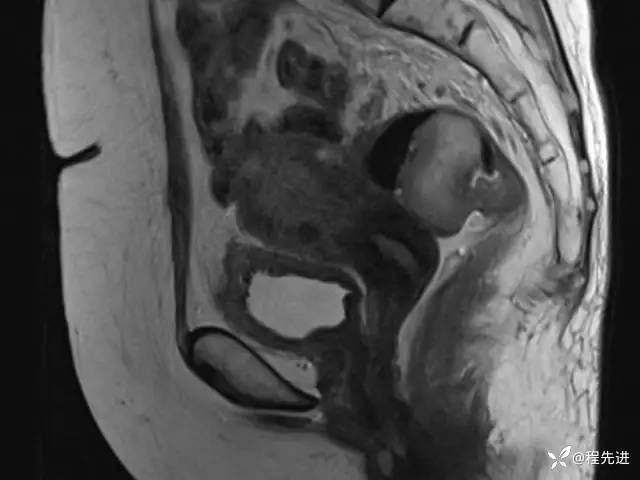

T2矢状位: